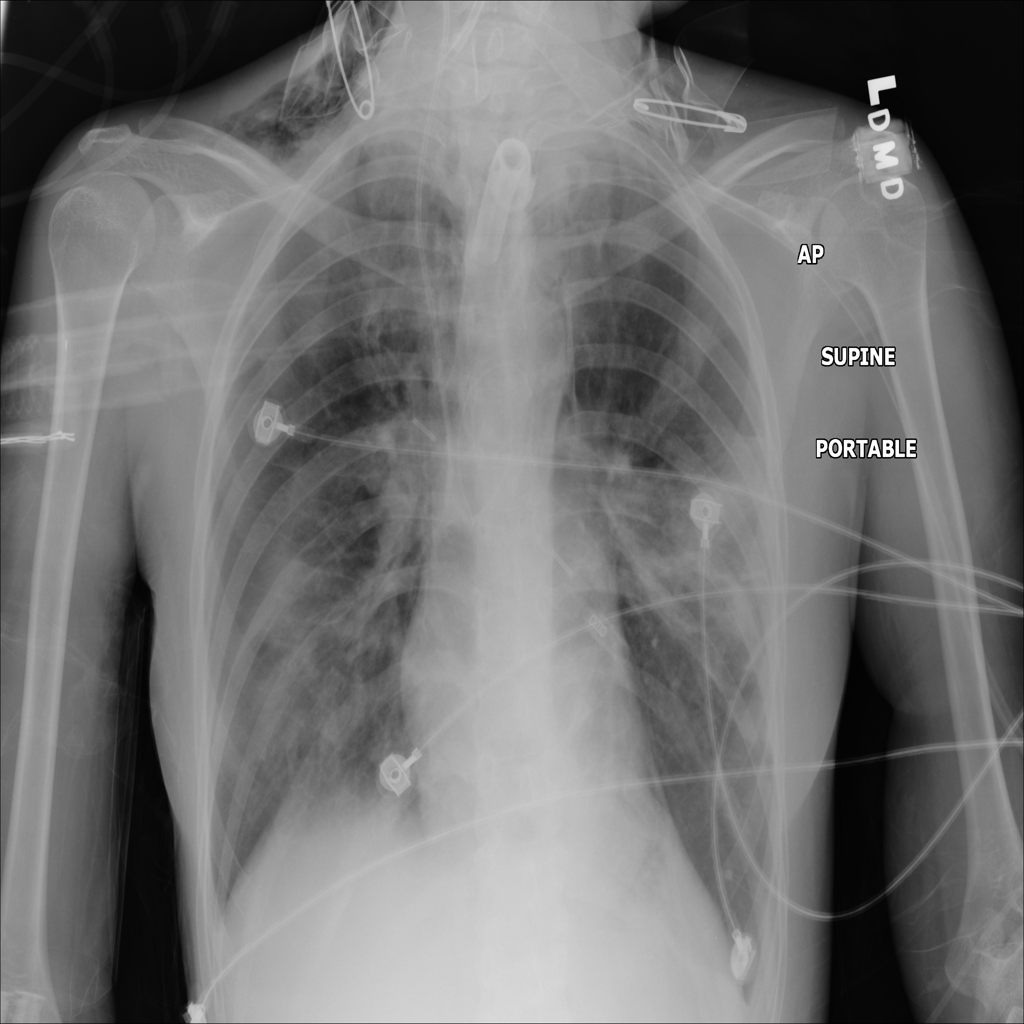

PAT-0E82 · IMG-000Emphysema

PAT-0E82 · IMG-000

AP